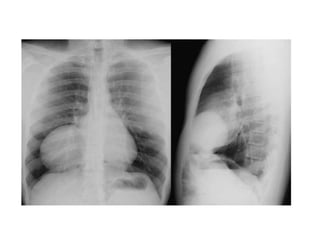

• #51 Paciente masculino de 63 años que refiere tos, disnea y dolor torácico derecho de aproximadamente siete días de evolución. El examen físico revela hipo ventilación en hemitorax derecho. Como dato positivo de laboratorio presenta VSG aumentada. Se solicita inicialmente una radiografía de tórax frente en la cual se observa, radioopacidad basal derecha con broncograma aéreo que borra el seno costofrénico homolateral. Engrosamiento pleural difuso que impresiona comprometer pleura mediastínica. Dados los hallazgos en la radiografía se decide ampliar el diagnostico solicitándole una TAC de tórax con contraste endovenoso en la cual se observa engrosamiento circunferencial pleural de hemitorax derecho. Atelectasia de segmentos inferiores con broncograma aéreo. Pequeña área líquida tabicada. Adenomegalias mediastinales en región prevascular, pretraqueal retrocavo y ventana aortopulmonar. Caja torácica sin alteraciones tomográficamente demostrables. Estructura y densitometría osteoarticular de l raquis dorsal normal. DIAGNOSTICOS DIFERENCIALES: • Engrosamiento pleural: Derrame organizado, hemotórax, piotorax, cirugía previa, radioterapia, exposición al Asbesto. • Tumores Benignos: lipomas, tumores fibrosos, esplenosis torácica. • Tumores malignos: MTTS de pulmón, mama, linfoma. • Mesotelioma maligno. DIAGNOSTICO DEFINITIVO: • MESOTELIOMA MALIGO